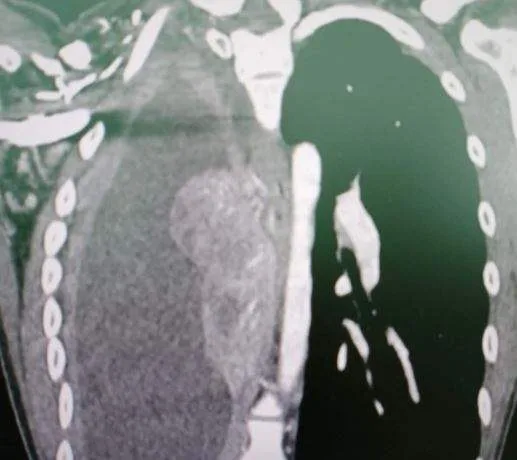

หญิงสาววัย 27 ปี ไม่มีประวัติการสูบบุหรี่ แต่ตรวจเจอมะเร็งปอด หลังมีอาการไอเหนื่อยนาน 2 สัปดาห์ – น้ำหนักลด 4 โล

กรณีนี้แสดงให้เห็นว่าแม้ผู้ป่วยจะไม่สูบบุหรี่และอายุยังน้อย ก็ไม่ได้หมายความจะไม่เป็นมะเร็ง เพราะมีผู้ป่วยมะเร็งปอดที่อายุน้อย ประมาณ 0.6 – 13% และเกิดกับผู้หญิงมากกว่าผู้ชาย

ผู้ป่วยที่อายุน้อย เช่น ต่ำกว่า 35 ปี, ต่ำกว่า 40 ปี, หรือต่ำกว่า 50 ปี สามารถพบมะเร็งปอดได้ มักไม่มีประวัติสูบบุหรี่ และผู้ป่วยมักมีอาการก่อนได้รับการวินิจฉัยค่อนข้างนาน เพราะผู้ป่วยมักจะไม่เฉลียวใจว่าจะเป็นมะเร็งปอด